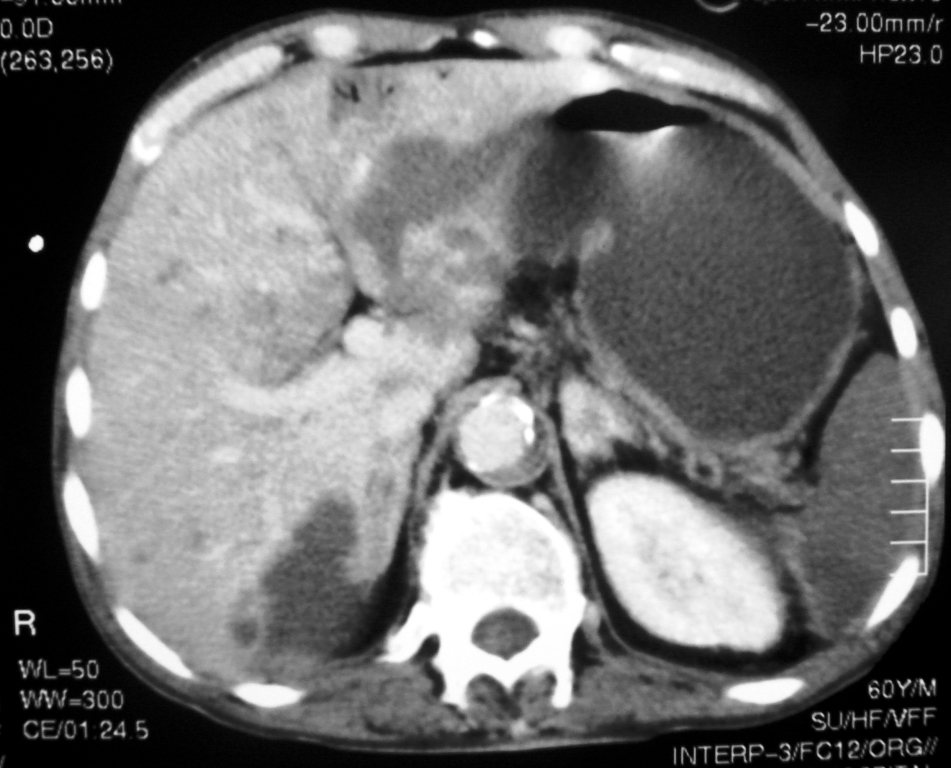

We describe the case of a 60-year-old diabetic man who was admitted to our hospital with keto-acidosis and rapidly developed sepsis and a mycotic abdominal aortic aneurysm (AAA) with branch involvement. Early and late findings on serial computed tomography (CT) examinations are presented. Awareness and recognition of early imaging findings associated with infectious aortitis and serial CT examination in cases of patients with sepsis and predisposing factors are essential for prompt diagnosis and treatment.